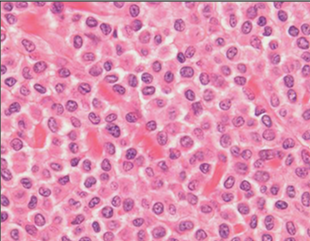

Question

Which type of round cell tumour is this? Note the bean shaped cells

Answer

• Mast cell tumour

• Plasmacytoma

• Histiocytoma

• Lymphoma